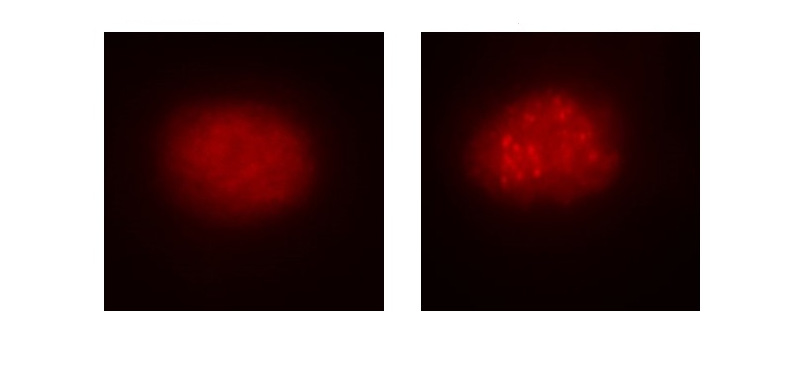

Desarrollan un modelo experimental para el estudio de un tipo de atrofia humana del nervio óptico